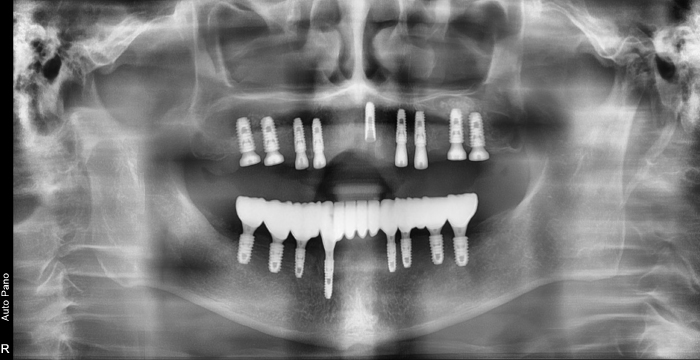

즉시 식립 임플란트 전후 사례

• 식립 전

식립 후